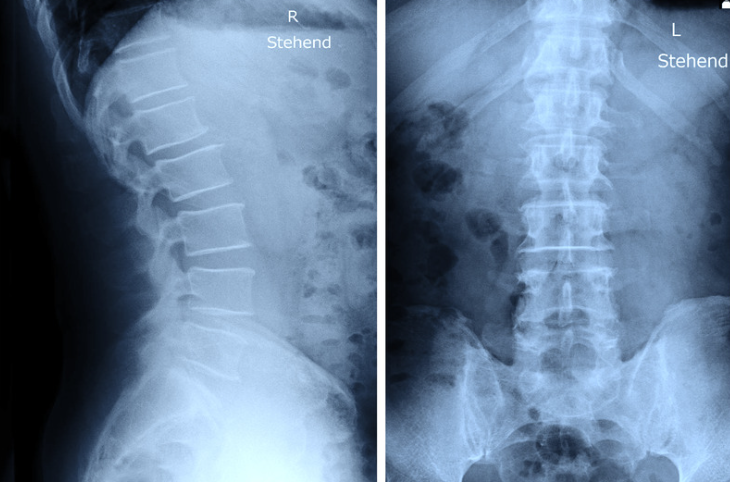

高齢の方の慢性的な腰痛の場合、変形性腰椎症の場合が多いです。基本的にレントゲンを撮って、腰骨の正面と側面、また前かがみや後ろに反らした状態で腰の並びやずれがないかをチェックします。

診断はレントゲンで行います。正面と側面を確認し、つぶれている腰骨がないかチェックします。腰骨がつぶれてなくても安心はできず、不顕性骨折と言ってレントゲンでわからない骨折もあるので、痛みが強い場合はMRIで診断することもあります。